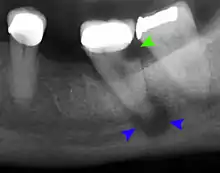

Apical abscess associated with roots of a lower molar.

Apical periodontitis is acute or chronic inflammation around the apex of a tooth caused by an immune response to bacteria within an infected pulp.[20] It does not occur because of pulp necrosis, meaning that a tooth that tests as if it's alive (vital) may cause apical periodontitis, and a pulp which has become non-vital due to a sterile, non-infectious processes (such as trauma) may not cause any apical periodontitis.[10]:225 Bacterial cytotoxins reach the region around the roots of the tooth via the apical foramina and lateral canals, causing vasodilation, sensitization of nerves, osteolysis (bone resorption) and potentially abscess or cyst formation.[10]:228

The periodontal ligament becomes inflamed and there may be pain when biting or tapping on the tooth. On an X-ray, bone resorption appears as a radiolucent area around the end of the root, although this does not manifest immediately.[10]:228 Acute apical periodontitis is characterized by well-localized, spontaneous, persistent, moderate to severe pain.[6]:125–135 The alveolar process may be tender to palpation over the roots. The tooth may be raised in the socket and feel more prominent than the adjacent teeth.[6]:125–135